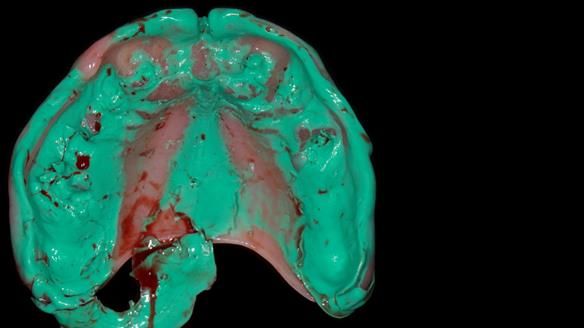

We provided her with an immediate upper denture (Mk 1), followed by a definitive metal-based upper denture (Mk 2). A lower removable partial denture was discussed, to be made only if needed once the upper treatment was complete. However, at review, this wasn’t necessary — Adnana had excellent neuromuscular control and function, even with a shortened dental arch (SDA).

Rowan, Sam Hesketh and Chris Hesketh provided the stunning technical work. I am very lucky to have them.

- Immediate denture (Mk 1) fitted the same day the teeth came out

- Definitive denture (Mk 2), metal-based and custom-designed for her face